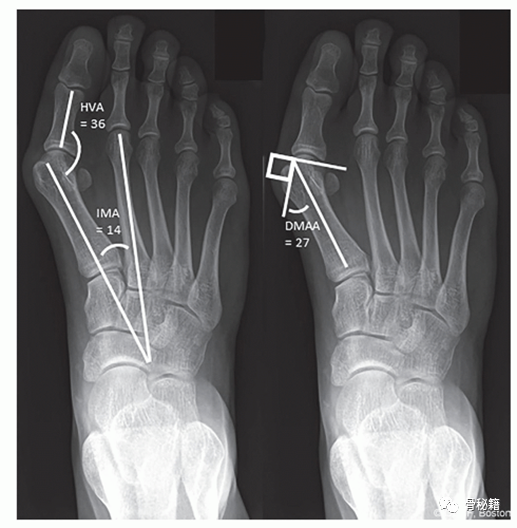

站立 AP 和足部侧位 X 光片对于评估畸形的严重程度和相关足部状况是必要的。应评估侧位 X 线片上的尾骨角和跟骨俯仰角,以及在 AP 视图上的距舟覆盖作为存在相关)。拇外翻畸形及其严重程度的表征基于测量结果HVA 评估第一跖骨干和近节指骨纵轴之间的角度。该角度应小于 15°。IMA 是第一和第二跖骨干之间的角度,是跖骨内翻程度的量度,应小于 9°。远端跖骨关节角 (DMAA) 测量第一跖骨远端关节面相对于其长轴的方向,通常小于 10°。还应评估跖趾关节的一致性。由于跖骨内翻,大多数青少年拇囊炎的 IMA 增加,DMAA 增加和跖趾 (MTP) 关节一致。

照片显示 (1) HVA、(2) IMA 和 (3) DMAA 的测量值。

DMAA,远端跖骨关节角;HVA,拇外翻角;IMA,跖骨间角。